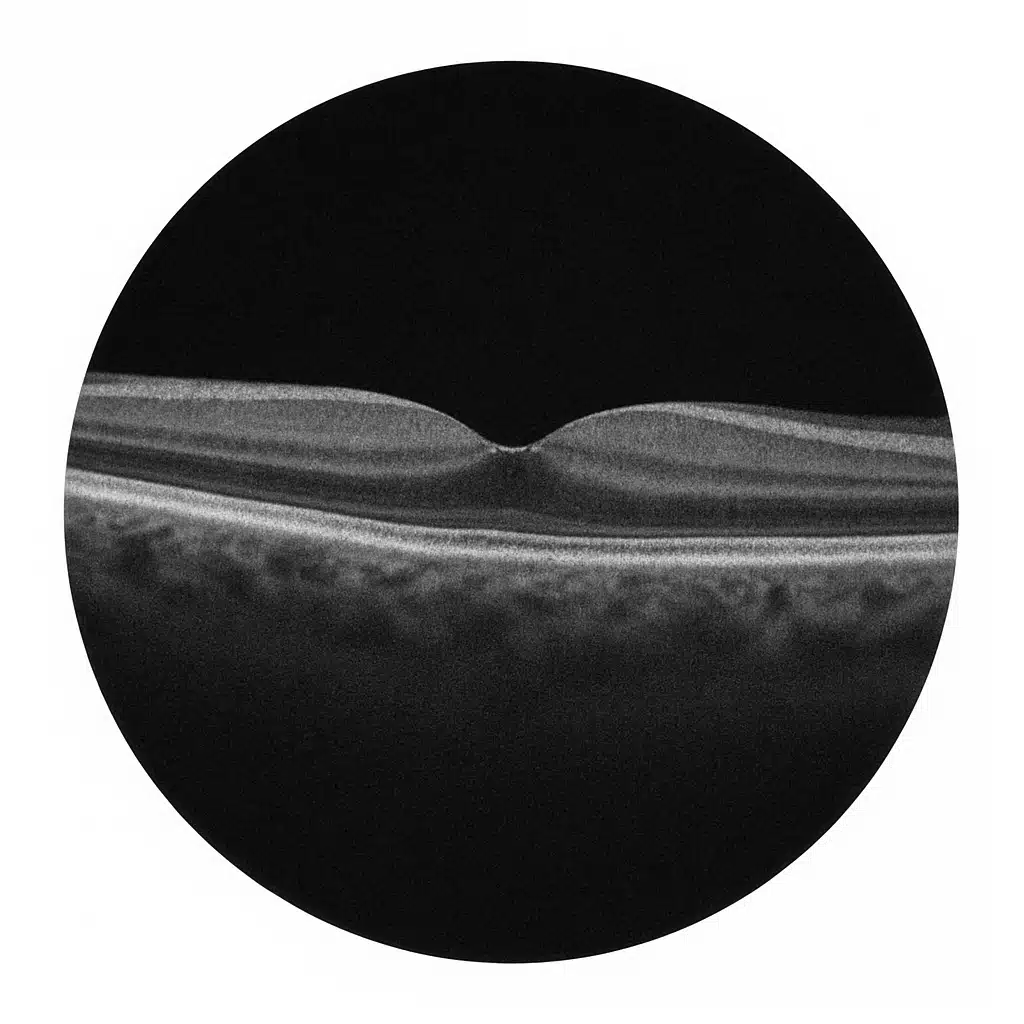

Tomographie en Cohérence Optique

Université de Toulouse